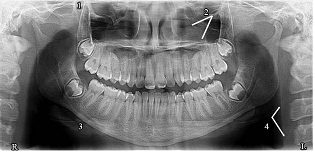

Assinale a opção que corresponde aos pontos anatômicos identificados pelos numerais de 1 a 4 na imagem radiográfica apresentada.